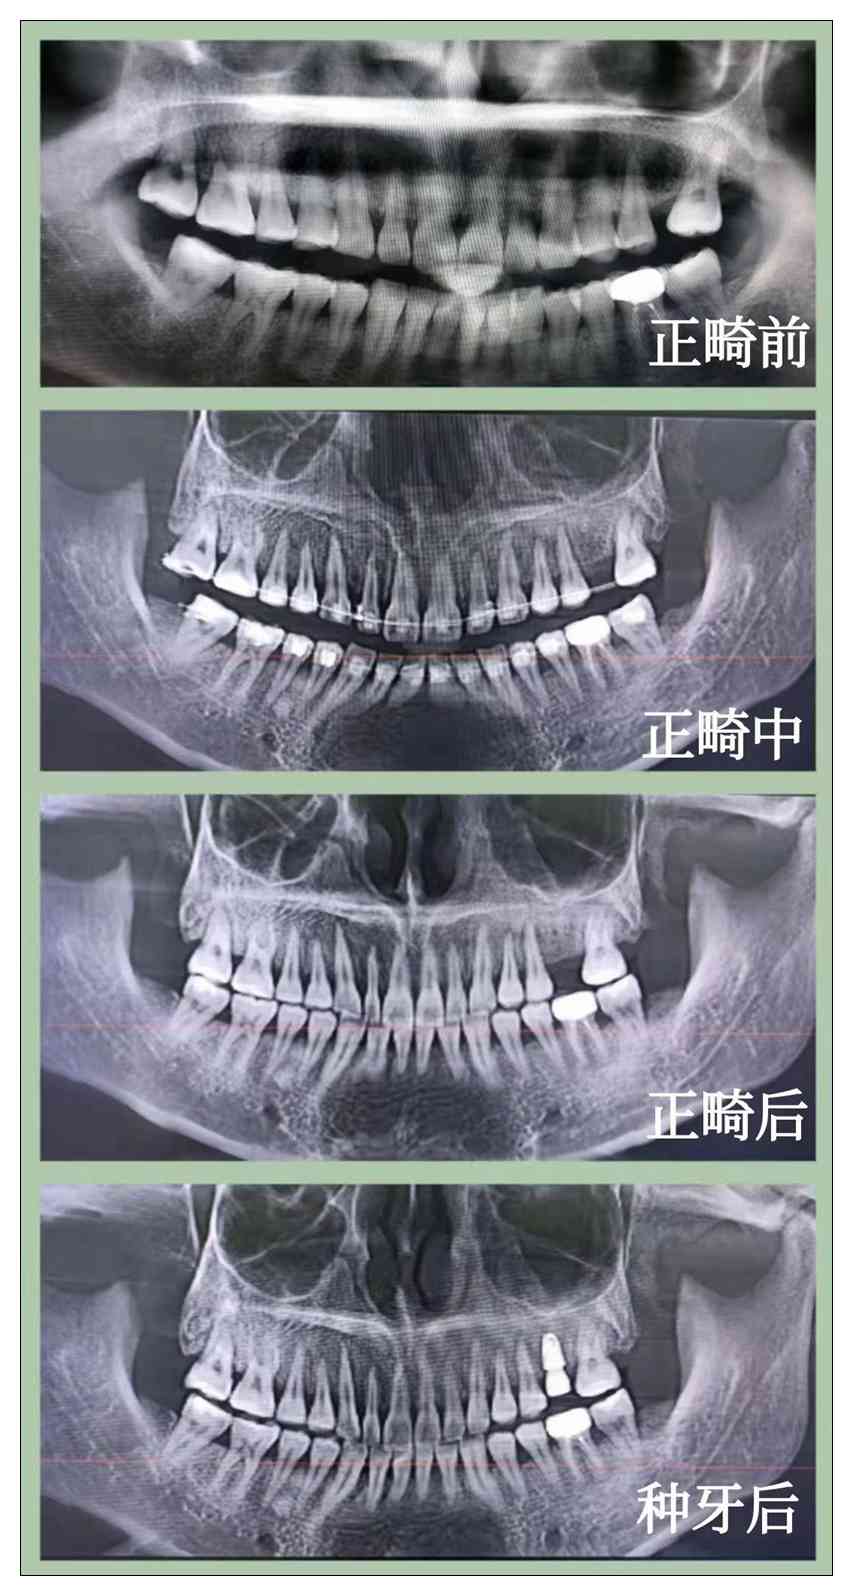

沈延飞口腔

凤城沈延飞口腔门诊部

服务宗旨:用心服务,精益求精。

愿成为您一生的保健牙医